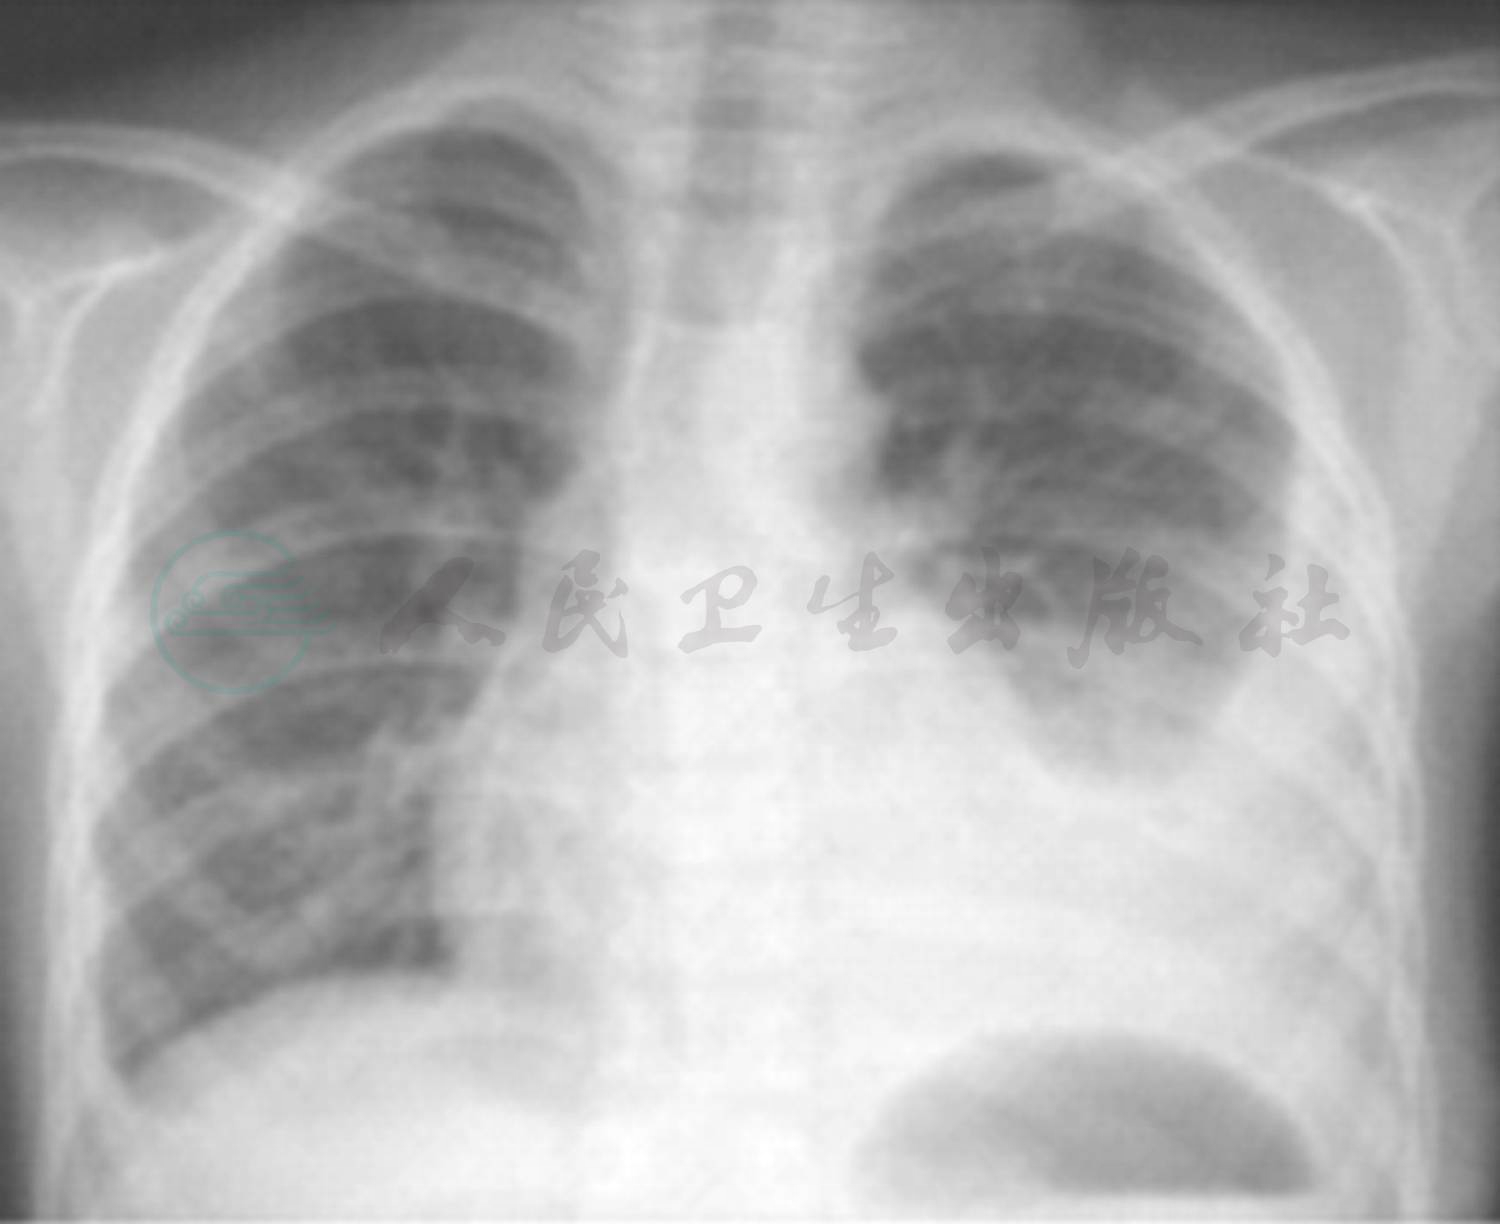

辅助检查:(2009年10月6日外院)胸部X线片:双肺纹理增强,双侧胸膜肥厚,肋膈角消失(图1)。(2009年10月28日外院)胸部X线片:双肺纹理增强,双侧肋膈角较前减轻(图2)。(2009年11月5日外院)胸片提示:左肺野第二三肋间以下可见外高内低致密影,左心肋膈角消失,右肋膈角变钝(图3)。(2009年11月14日外院)胸片提示(图4):左侧胸腔积液较前减少,右侧胸膜肥厚,双下纹理增强。

图1 双肺纹理增强,双侧胸膜肥厚,肋膈角消失